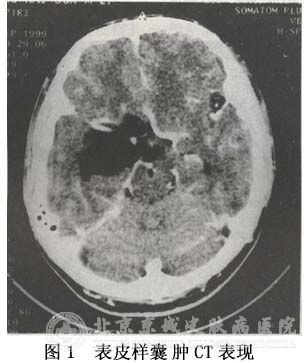

北京京城皮肤医院的皮肤专家蔡教授介绍说,表皮囊肿是神经管滞留引起的一类疾病。里面充满了角质所以又名为角质囊肿。临床上,为了检查表皮囊肿的状况,会检查颅骨X线平片,CT,MRI等项目。

通过颅骨X线平片检查我们会发现除了颅内压力增高,还出现岩骨尖吸收。颅中窝表皮样囊肿有岩骨嵴破坏或者岩骨尖。在板障内表皮样囊肿可见骨质被破坏,骨密度变高等,个别甚至出现了钙化斑。透过CT我们发现影像特征表现为低密度区,如果发现有脑桥小脑角则是表皮囊肿癌话的一个标志。MRT是检查颅后窝是否有表皮样囊肿,能够显示出ct无法显示出的肿瘤范围,某占位效应,血管移位等。